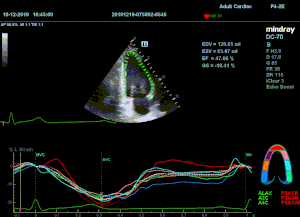

Всё изменилось с появлением технологии Speckle-tracking. Ультразвуковые приборы компании Mindray DC 8, 70, 80, Resona 6,7 оснащены данной функцией. Для использования необходим ЭКГ-канал. В чем же смысл данного технологического новшества? Прибор использует видео петли сечений миокарда, разбивает миокард на точки со стабильной визуализацией – speckle, и затем производит слежение каждой точки в течении нескольких сердечных циклов. Изменение пространства между точками дает нам представление о возможностях деформации миокарда, как продольной – Longitudinal Strain, так и деформации скручивания – торсии и Radial Strain.

Как работать с данным методом? Для Longitudinal Strain необходимо записать видео петли апикальных сечений в память прибора: 4С, 3С, 2С. Для повышения качества трекинга рекомендуется производить запись на выдохе пациента. Затем произвести разметку по линии эпикарда, перикарда и центра миокарда. Нажатием кнопки «начать слежение» активируется программный алгоритм, видео петля оживает вместе с размеченными точками-speckle’ами. При необходимости производится коррекция. После анализа всех трех сечений можно получить данных продольной деформации как в среднем значении, так и по каждому сегменту миокарда левого желудочка. Нормальным показателем считается Longitudinal Strain -20%. Нижней границей -14%.

Видео примеры на приборе Mindray DC 70